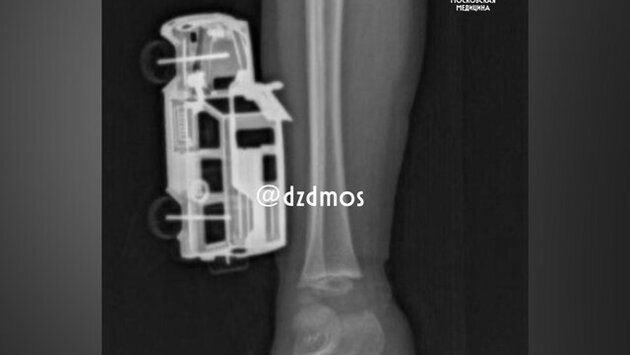

Врачи в Москве спасли 4-летнего ребенка, у которого в ноге застряла металлическая игрушечная машинка в голени, рассказали в телеграм-канале Депздрава столицы.

По словам родителей, ребенок прыгнул с кровати и неудачно приземлился на игрушку. Она повредила мягкие ткани правой голени, а части игрушки вошли до подкожножировой клетчатки. Родители вызвали скорую помощь, и ребенка госпитализировали в больницу Сперанского.

Травматолог-ортопед отделения экстренной хирургической помощи Магомед Шихахмедов рассказал, что мальчику сделали рентгенографию, так как нужно было исключить повреждения костей и понять, насколько глубокие повреждения.

После этого игрушку удалили и выполнили хирургическую обработку раны. Уже через сутки мальчика выписали домой под амбулаторное наблюдение.